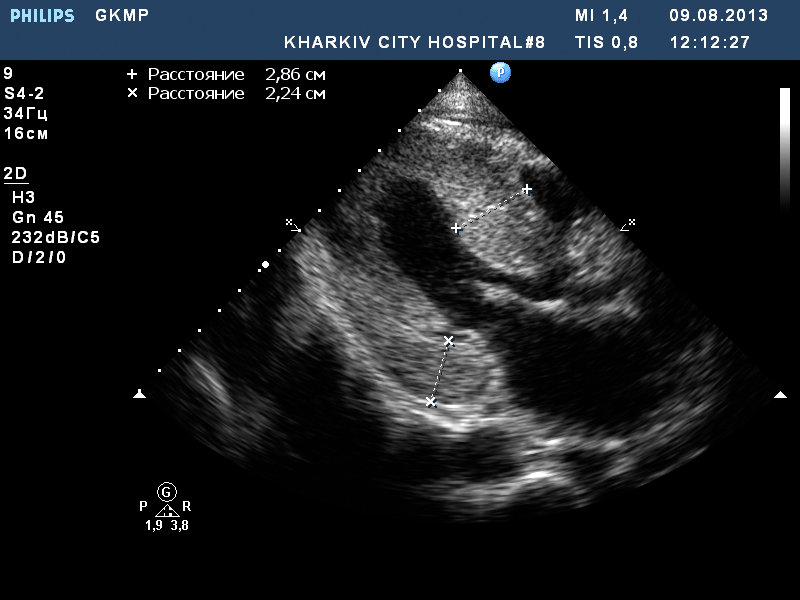

ГКМП

ГКМП. обструкции кровотока в выносящем тракте левого желудочка нет.